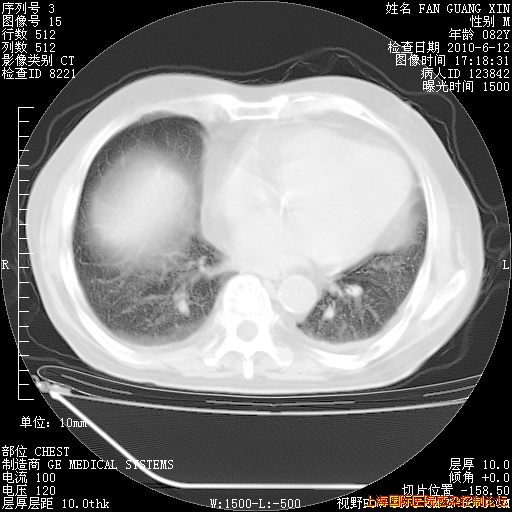

6月12日纵膈窗

整整相隔30天的肺部CT好像有所好转啊。甲强龙减量第3天,需要观察体温。

海管,自昨日你和我通完话后,不知您岳父消化道症状有无缓解?体温怎样?阅读7.12日胸部ct,个人认为目前激素治疗是有效的,甲强龙减量是适宜的。因在抗痨治疗,需密切观察肝功、肾功能和血常规。不过,老年、长期住院和大量使用激素,很担心菌群失调发生